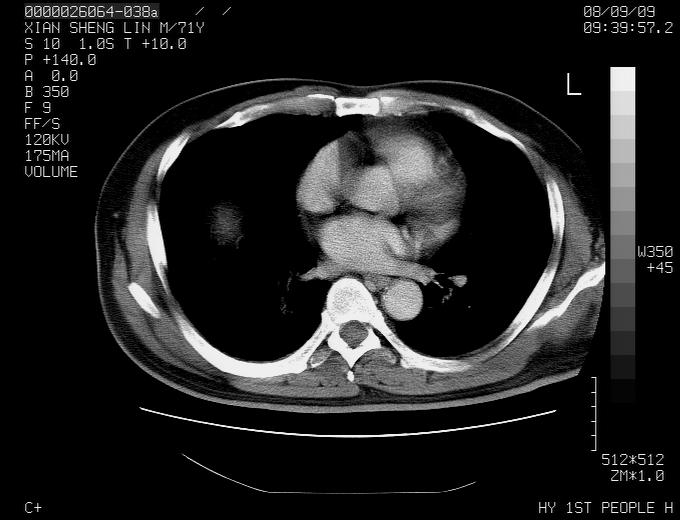

标题: CT15869:男性,71岁,因咳嗽而就诊,请讨论右上肺病变性质 [打印本页]

标题: CT15869:男性,71岁,因咳嗽而就诊,请讨论右上肺病变性质

患者,男性,71岁,因咳嗽而就诊,

典型的右肺中心性肺癌并纵隔淋巴结转移

考虑右肺中心性肺癌并右肺门及纵隔淋巴结转移。

1,右肺中心型ca,气管隆突旁淋巴结转移。

2,右膈明显抬高,建议肝脏扫描排除转移或原发灶。